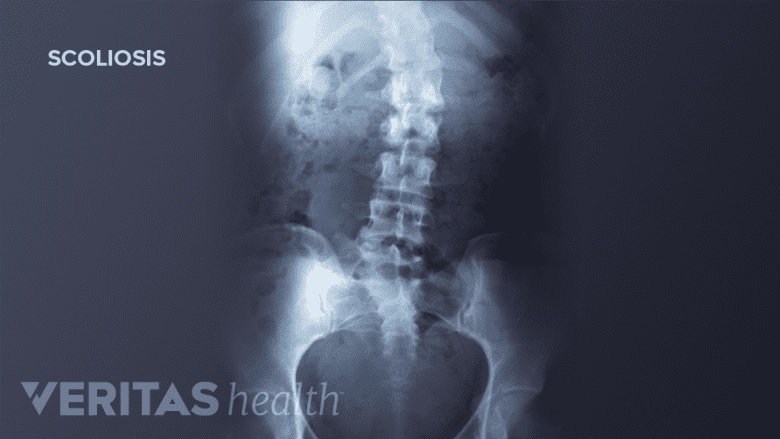

An official diagnosis of idiopathic scoliosis requires X-ray confirmation of the abnormal lateral curvature and spinal rotation, as well as ruling out other possible causes for the deformity (such as Scheuermann's disease, juvenile disc disorder, or ankylosing spondylitis).

The lateral curve of scoliosis is described by the Cobb angle. Using an X-ray of the full spine, the Cobb angle is found by drawing a perpendicular line from the spine’s most-tilted vertebra above the sideways curve’s apex and a second perpendicular line from the most-tilted vertebra beneath the apex. The angle formed where those two lines meet is the Cobb angle.

A Cobb angle of at least 10 degrees is typically considered the borderline for a scoliosis diagnosis.